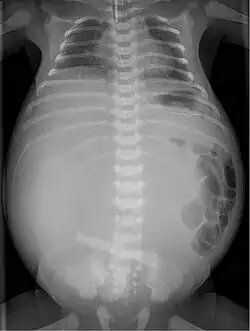

Da noch keine bakterielle Besiedlung des Darmes stattgefunden hat, ist die resultierende Entzündung der Bauchhöhle steril als Fremdkörperreaktion. Durch rasch einsetzende Kalkablagerung finden sich im Röntgenbild des Neugeborenen charakteristische zarte linienförmige Verkalkungen.

Es kann sich auch eine Pseudozyste ausbilden, die eine den Darm je nach Größe mehr oder weniger verdrängende Raumforderung abbildet. Wenn die Perforation bis nach der Geburt bestehen bleibt, kann auch Gas austreten und eine bakterielle Entzündung entstehen.